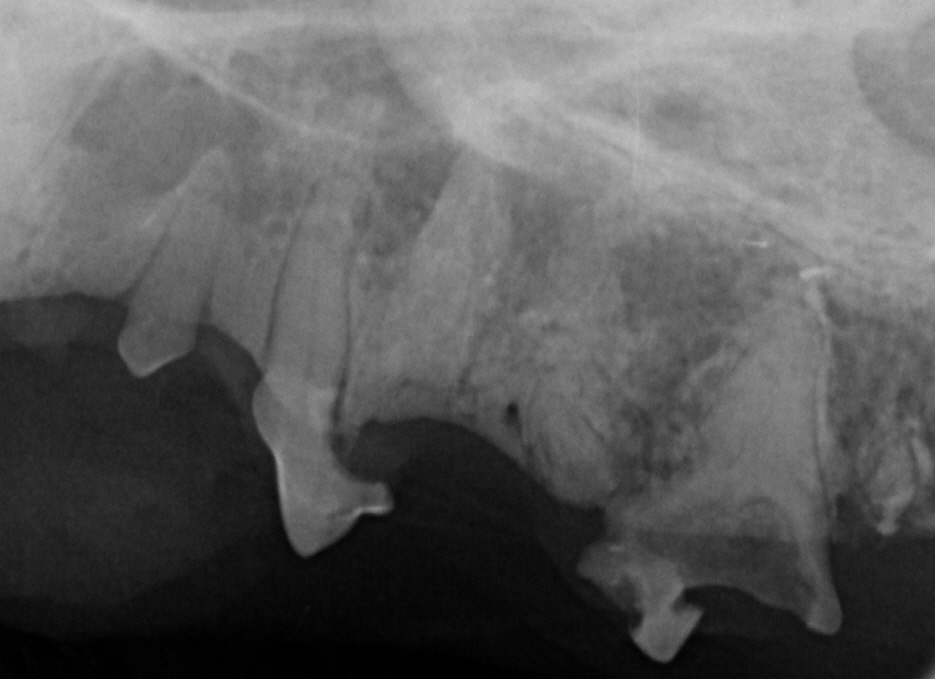

Bedeutung des Dentalröntgens:

Dentalröntgen ist unerlässlich, um resorptive Läsionen sicher zu diagnostizieren. Viele Läsionen sind nur unter dem Zahnfleisch sichtbar und können bei der reinen Mauluntersuchung nicht diagnostiziert werden. Röntgen ermöglicht:

- Erkennung von frühen unter dem Zahnfleischrand befindlicher Veränderungen

- Unterscheidung der Läsionstypen und somit Planung der geeigneten Therapie (Extraktion oder Kronenamputation)